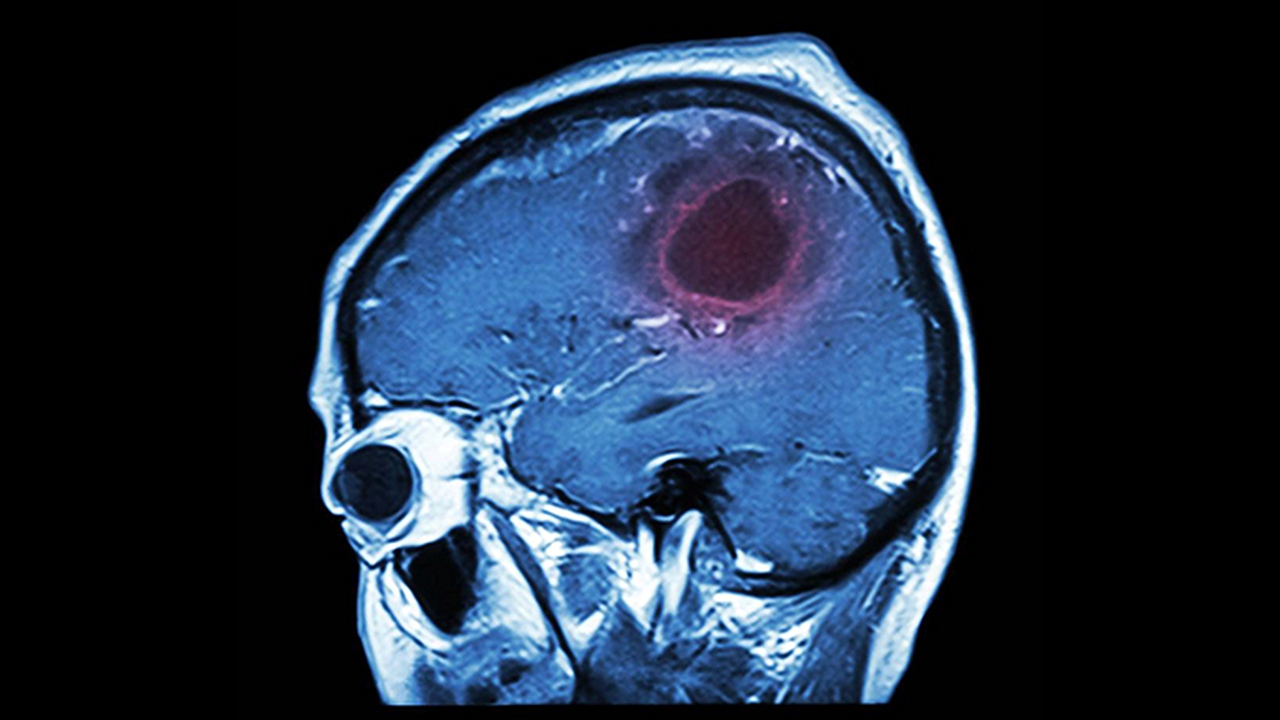

肺癌是一种常见的恶性肿瘤,其发病原因复杂,包括吸烟、环境污染、职业暴露、遗传因素等。早期诊断和规范治疗对提高患者生存率至关重要。目前,肺癌的治疗方法主要包括手术、放疗、化疗、靶向治疗和免疫治疗等。